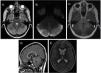

The second and third patients both sought care for headache of approximately a week's duration that had intensified, interfering with daily activities and disturbing sleep, and accompanied by vomiting. The findings of the physical examination and the CT scan were normal in both, and they were both admitted to hospital for analgesia. Due to lack of response, they underwent evaluation by cranial MRI (Fig. 2), which led to diagnosis of AC. The management of AC consisted of monitoring and steroid therapy. The patients responded well, with improvement of symptoms and no complications, so they were discharged with a prescription for a tapering course of steroids. There was no evidence of sequelae in the follow-up evaluations. The follow-up MRI confirmed the resolution of the mass effect.

Head MRI. (A) T2-weighted axial plane: hyperintensity and swelling in both cerebellar hemispheres. (B) Generalised restricted diffusion. (C) T1-weighted axial view: absence of enhancement after administration of gadolinium contrast. (D) T1-weighted sagittal view: descent of cerebellar tonsils into foramen magnum, anterior displacement of the brainstem and mild caudal compression of the cerebral aqueduct and the fourth ventricle. (E) Secondary supratentorial ventricular dilation.